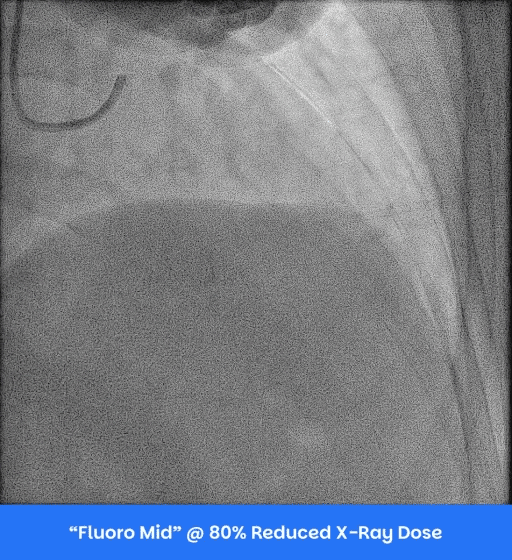

Investigational Pig Angiogram

@ 25% Contrast CBSET Lexington MA

Iodinated Contrast was diluted by 75% with saline solution.